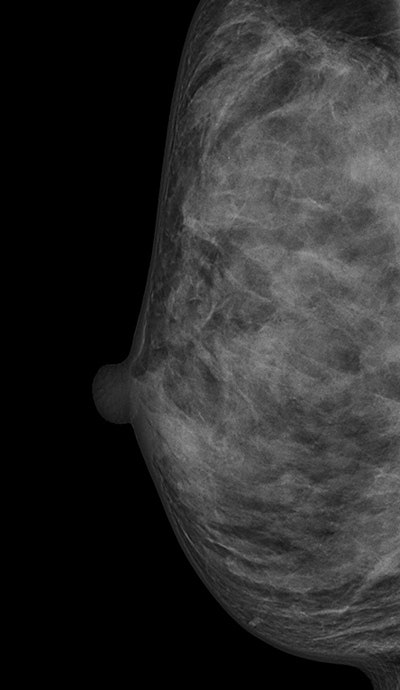

Digital mammogram of an ACR 3 dense breast. All images courtesy of Dr. Stefanie Weigel."We suppose that the screening performance should not be assessed in women with 'dense breast,' commonly derived from conflating women with ACR [American College of Radiology] 3 and ACR 4, but rather that it seems advisable to separate these two categories due to their different performance," they noted (European Radiology, 7 November 2016).

ACR's BI-RADS classifies breasts as almost entirely fatty (ACR 1), scattered areas of fibroglandular density (ACR 2), heterogeneously dense (ACR 3), or extremely dense (ACR 4). Heterogeneously dense and extremely dense are usually combined into one category of dense breasts. They are indicated by quartile ranges of percentage dense tissue more than 50% and as possibly obscuring small masses and lowering the sensitivity of mammography.

Most of the dense breasts are classified as heterogeneously dense and the frequency of breast densities is reported as 10% fatty, 40% scattered, 40% heterogeneously, and 10% extremely dense, the study authors explained. Higher breast density is associated with decreased mammographic sensitivity and specificity, as well as with increased breast cancer risk. Breast density may also be a factor that contributes differentially to screen-detected breast cancers and interval breast cancers, they added.